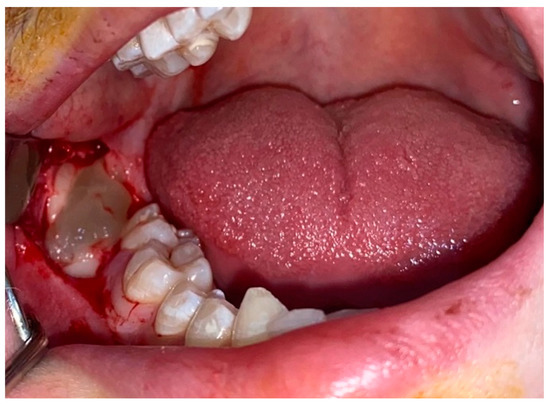

Comparative Investigation of Anti-Inflammatory Effect of Platelet-Rich Fibrin after Mandibular Wisdom Tooth Surgery: A Randomized Controlled Study

2. Materials and Methods

2.1. Operations